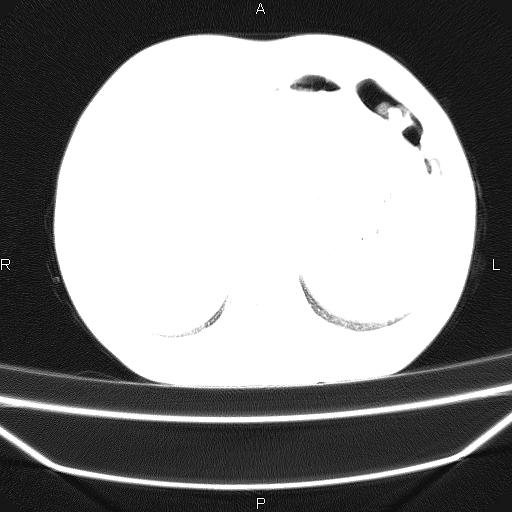

患者,男,40岁。间断发热,咳嗽二十余日。体温最高达38.9° 在当地诊所抗炎治疗三天后体温降至正常,患者自行停药。今又发热。胸片示,左下肺阴影。

左下肺片状高密度影,境界模糊,密度不均,考虑感染性病变可能性大,建议抗炎治疗后复查。左肺门增大,不除外占位性病变,必要时支气管镜检。

考虑感染性病变可能性大,抗炎后复查,占位不排除。

建议强化或纤支镜观察,考虑肿瘤性病变可能性大